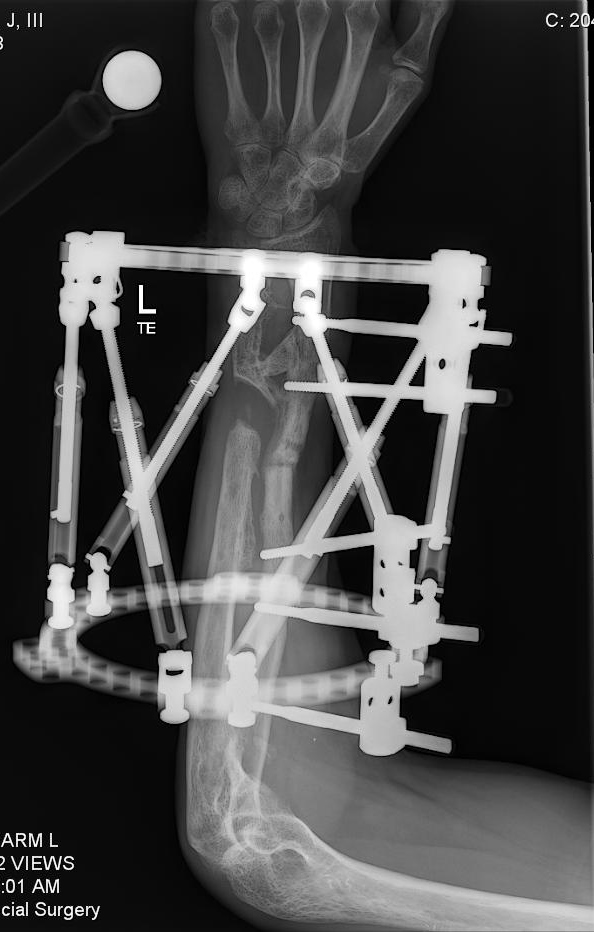

I was in a serious car accident in 2010 and broke both arms, both legs, pelvis, vertebrae and ribs. I was flown to a trauma 2 center in NJ. After being put back together from the initial accident, I healed for 3 months until I searched out Dr. Rozbruch at HSS. My right leg was short and angled due to the trauma. My left arm was a non-union and deformed. Sitting with Dr. Rozbruch for the first visit was amazing. He was confident in time that all of my issues could be repaired. It took multiple surgeries but a couple years later and he was right, HSS and Dr. Rozbruch fixed every single issue. I went from being told I may never walk again at the original hospital to now back to surfing, water skiing and playing basketball. Never in a million years did I think I would have such an incredible outcome. To add to the already stellar Dr. Rob Rozbruch and HSS, I became friends with Dr. Rob Rozbruch and together we created a new product and company over the past 5 years to aid patients in their healing. It is a device that aids patients in healing from lower limb injuries.